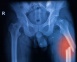

Atypical femur shaft biphosphonate fractures

Bisphosphonates are used to treat postmenopausal and glucocorticoid induced osteoporosis, Paget’s disease of bone and malignant hypocalcaemia. They have been related to the atypical femur shaft fracture.

We present a case of an 83-year-old woman on long term bisphosphonates presenting with atypical femur...